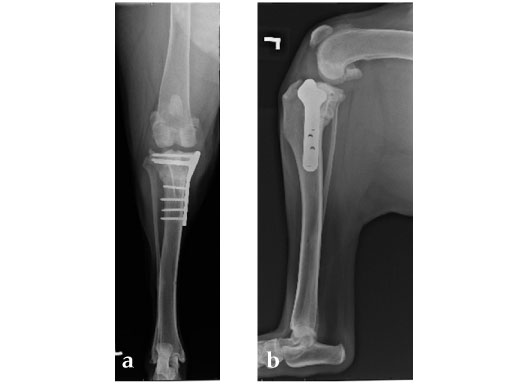

Case 2: Four-year-old English bulldog

(Case provided by Brian Beale, Houston, USA)

A four-year-old, female, spayed, 33 kg English bulldog had a CrCL tear and a medial patellar luxation. The small stature 3.5 mm TPLO plate was perfect for this dog due to the small profile of the bone and the need to use a heavier plate (3.5 vs a 2.7 mm). In the past, veterinary surgeons have been forced to either squeeze the standard TPLO 3.5 mm plate on the bone or use an undersized TPLO 2.7 mm plate. In this patient, the shorter and smaller profile head of the small stature TPLO 3.5 mm was perfect.